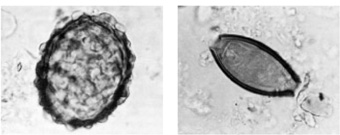

5 Microscoopfoto van twee wormeieren, ongeveer 1000 maal vergroot, uit de ingewanden van een veenlijk (vergelijk afbeelding 4). In 1984 werd in Lindow Moss te Cheshire, Engeland, een veenlijk gevonden, nu bekend als de Lindow Man. De C14-dateringen van het lichaam en van het omringende veen lopen helaas uiteen, maar de Lindow Man moet in ieder geval in de late bronstijd of ijzertijd gedateerd worden. In zijn ingewanden werden wormeieren aangetroffen, en wel de hier afgebeelde Ascaris lumbricoides, de spoelworm (links), en de Trichuris trichiura, de zweepworm (rechts), beide bekende darmparasieten. Het voorkomen van de Ascaris lumbricoides bij de mens wordt in verband gebracht met de domesticatie van het varken. De besmetting met deze parasieten is wijd verspreid in tijd en ruimte, maar de indruk bestaat dat in Europa in de periode van ijzertijd tot vroege middeleeuwen bijzonder veel mensen ernstig besmet waren.